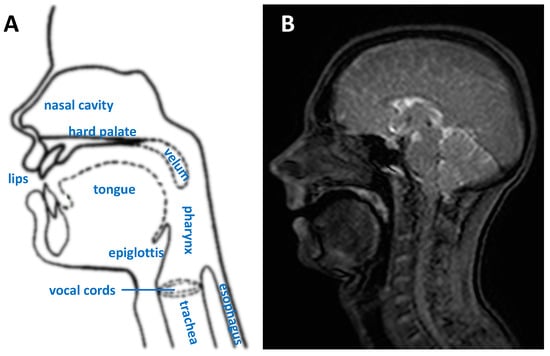

1.1. Upper Vocal Tract and Dynamic Imaging Rationale

- Binary masks of the whole head with the vocal and speech organs visible were created using thresholding from the heads and some user input to ensure the upper respiratory tract remains distinct but that regions with zero value are filled in non-speech organs.

- Manually select a region containing each speech articulator. It must be sufficiently large to allow for a full range of movement of an organ of interest (such as the velum or tongue) and is outlined directly onto the image.

- Automatically segment and create a mask for each organ of interest at each time point, using the Hadamard product of the head mask and organ of interest mask at each time point, an example for the velum can be seen in Figure 3. This results in binary masks for each of the speech organs of interest for each frame in the original dynamic image set.